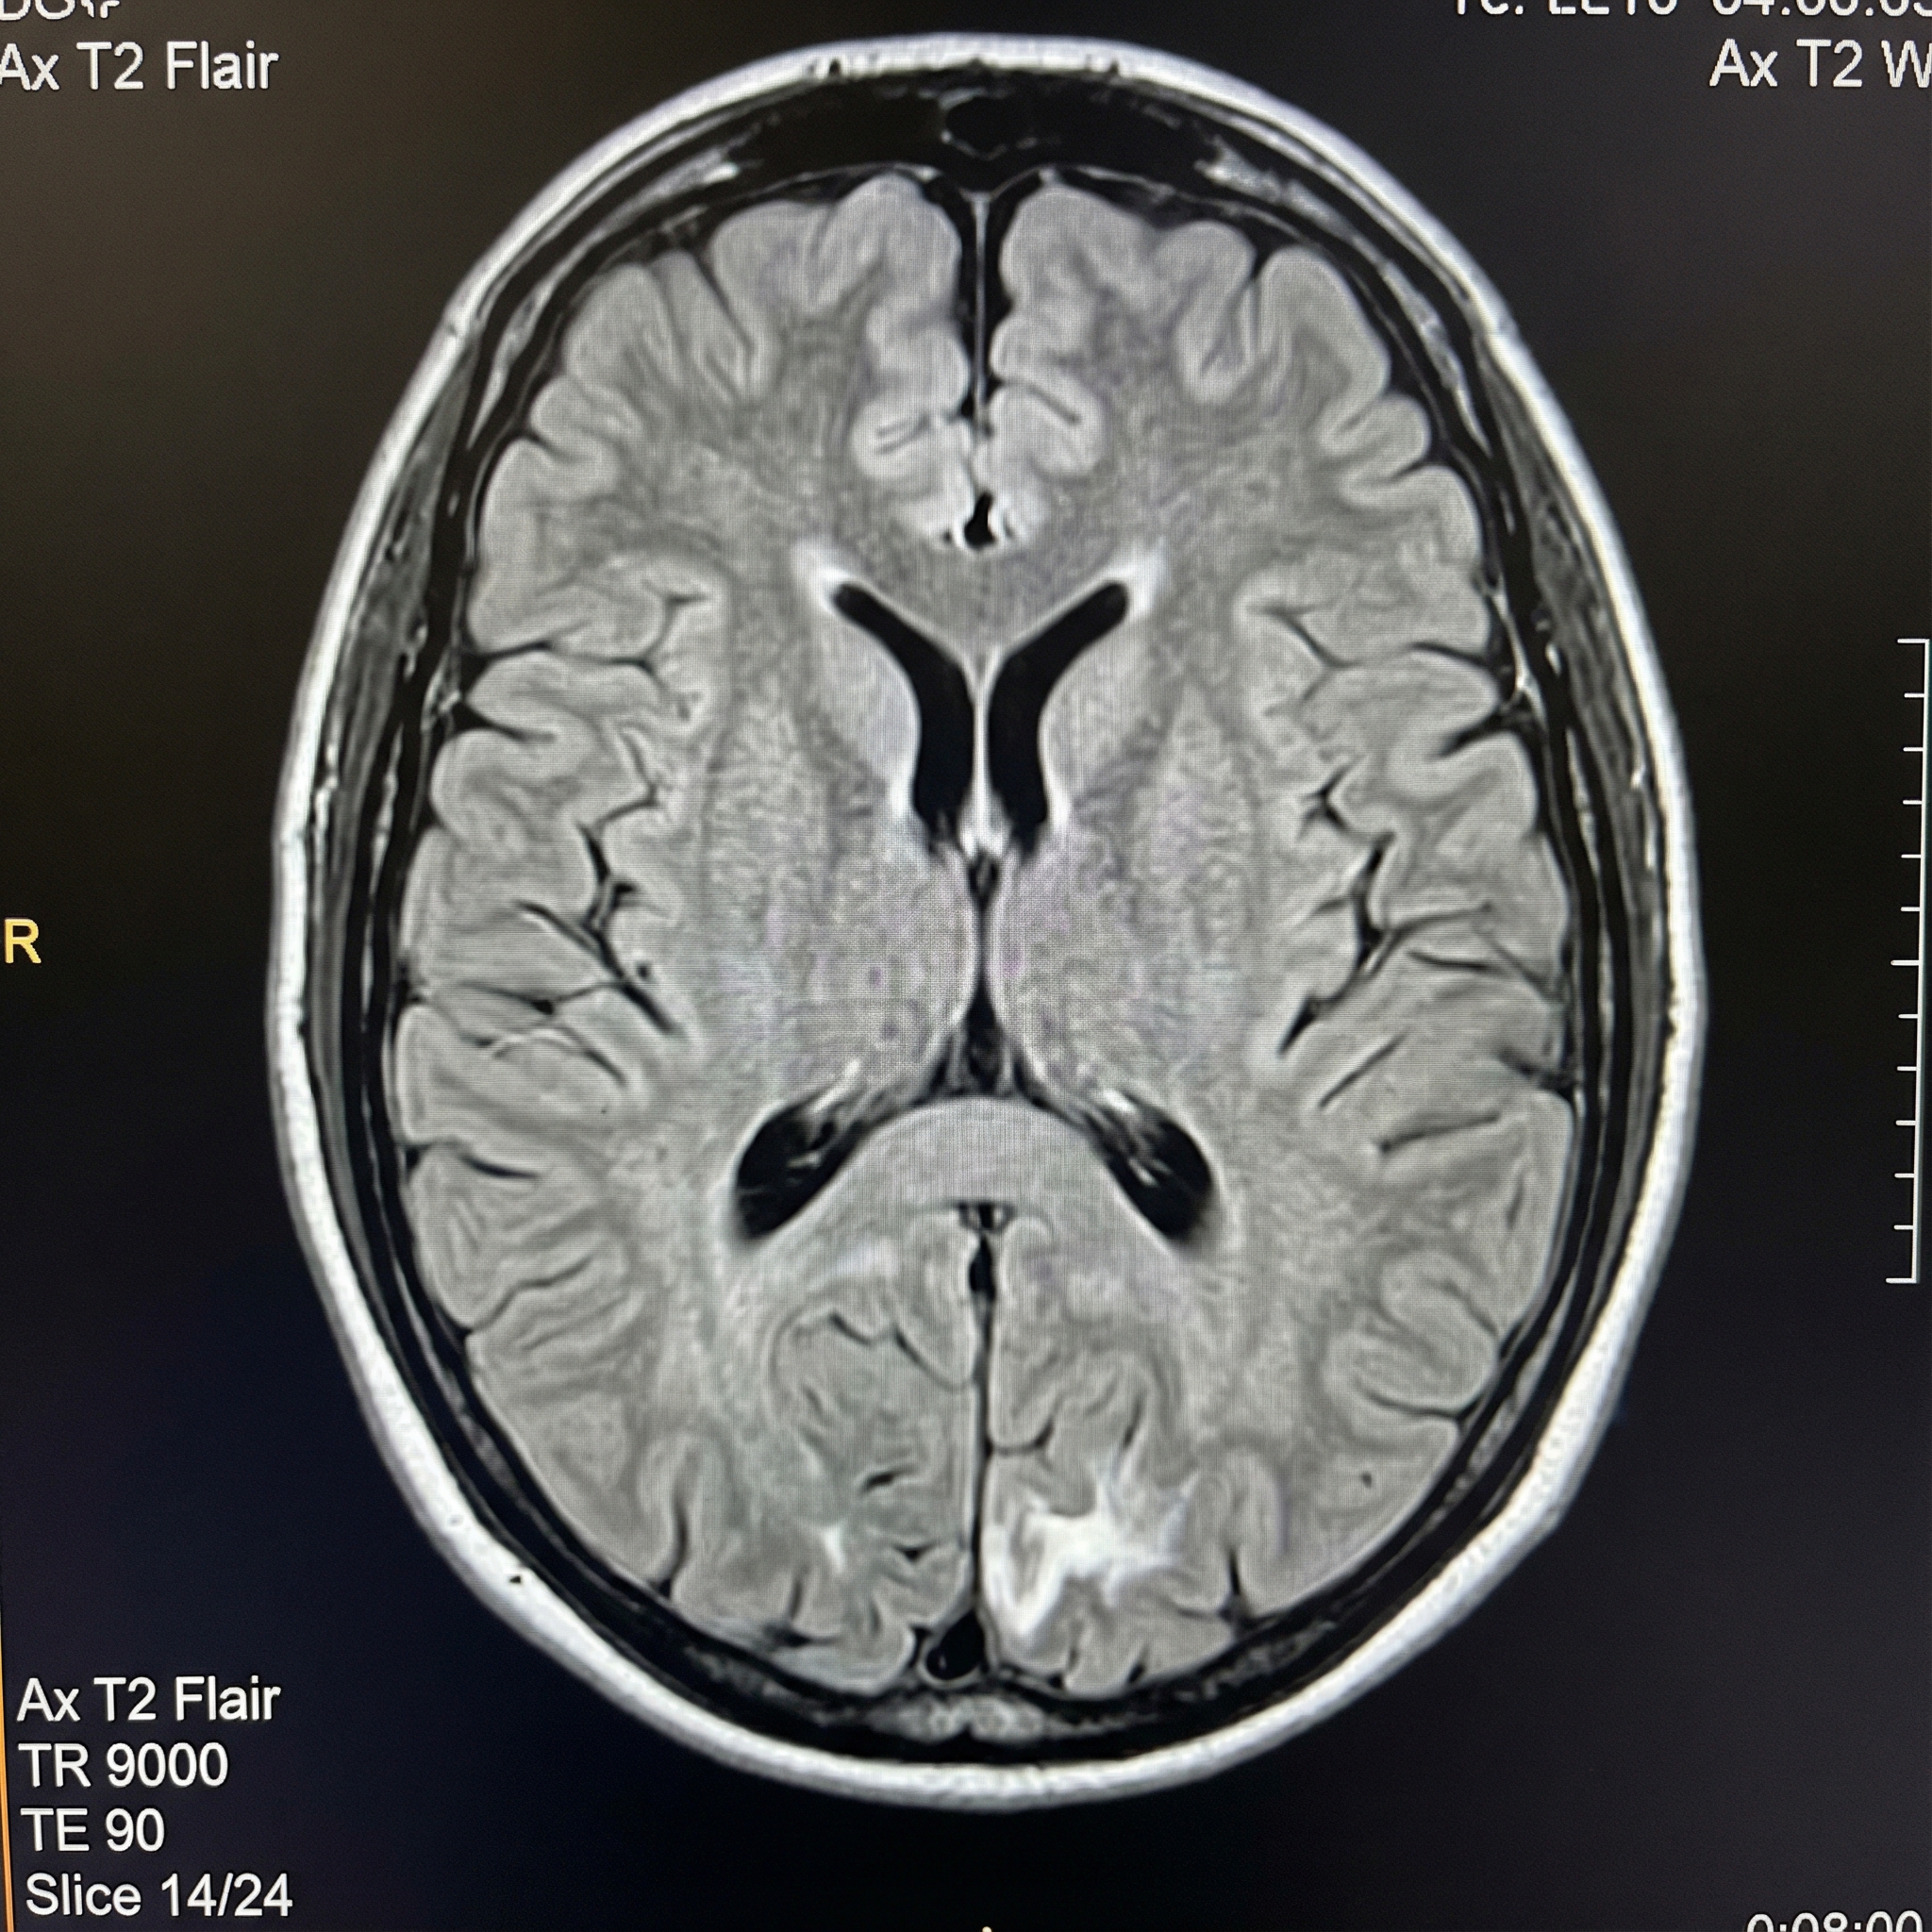

Clinical Images

Clinical images may be augmented to enhance pathology and clinical findings for educational clarity. All images are reviewed for accuracy by board-certified specialists to ensure broader pathology coverage across every subspecialty.